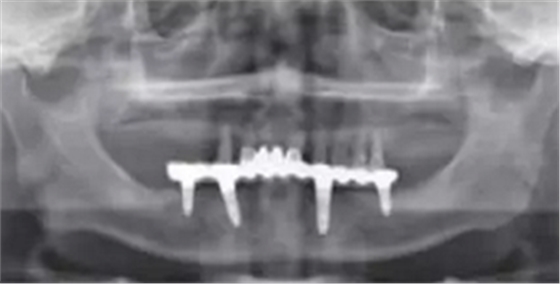

影像學(xué)檢查:下頜修復(fù)體與種植體邊緣密合,種植體周圍并無明顯異常,14、13、21、22、24、25見根尖陰影,牙槽骨吸收至根尖1/3。23見牙周膜增寬影,牙槽骨吸收至根中1/2(圖2,3)。診斷:上頜牙列缺損(15、16、17、26、27缺失);上頜廣泛性重度牙周炎;14、13、21、22、25根尖周炎。

圖3 術(shù)前曲面斷層全景片檢查

術(shù)后曲面斷層全景片(圖19)可見種植體在上頜位置較為理想,同時(shí)可見臨時(shí)義齒種植體開孔位置在13、23舌側(cè)、16、26牙合面近中,上下頜咬合關(guān)系理想。患者對(duì)種植臨時(shí)修復(fù)義齒滿意。

圖19 即刻修復(fù)后全景片